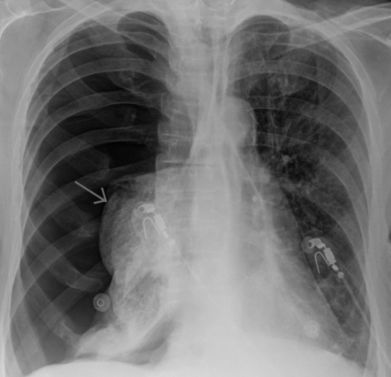

Пневмоторакс

Патологическое состояние, при котором в плевральной полости накапливается воздух, сжимает легкие и нарушает дыхание. При большом объеме воздуха происходит смещение сердца и крупных сосудов, что приводит к серьезным нарушениям кровообращения и дыхания.

Характер и локализация боли

При пневмотораксе возникает острая боль в грудной клетке, усиливающаяся при вдохе.

Иногда боль иррадиирует в плечо и спину со стороны пораженного легкого.

Диагностика включает:

- осмотр пациента;

- рентгенографию грудной клетки;

- компьютерную томографию;